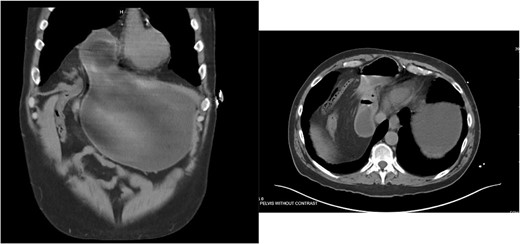

Care was taken to avoid injury to the pleura and the pericardium. Once the sac was reduced, the defect’s size was measured as 9 cm in horizontal length by 4 cm in vertical dimension. Primary closure of the defect was performed with a running 0 V-loc absorbable 180 suture.

Polypropylene ProGrip mesh was then cut to size to cover the primary defect. It was cut to 14 cm in horizontal dimension by 7 cm in vertical dimension, with rounded edges (Fig. 5).

Once it was in an appropriate position to cover the defect, attention was turned to the peritoneal flap closure with a running 3–0 V-Loc suture.

He underwent a CT scan ten months after surgery for flank pain with suspected nephrolithiasis, which demonstrated the successful repair (Fig. 6).